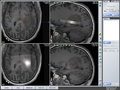

Project Title: Generation of a hybrid MR-Spectroscopic (MRS) dataset under 3DSlicer

Generating a hybrid MR-Spectroscopic (MRS) dataset under 3DSlicer that can be used for fusion with the anatomic dataset under iPlan of BrainLAB in AMIGO. A hybrid MR-Spectroscopic dataset can for example be used for biopsy targeting in brain tumors. Besides, the metabolic concentrations and ratios can help to diagnose lesions.

Loaded/integrated processed chemical shift-MRS data from Uni. Marburg into Slicer4.